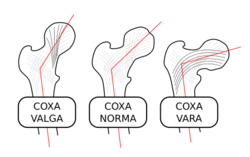

الردف أو الورك Hip منطقة من الجسم تقع بين الجذع والفخذ. ويتشكل مفصل الردف من عظم الردف الذي يتكون من ثلاثة عظام: عظم الحرقفة وعظم الإسك وعظم العانة، ومقدمة عظم الفخذ. وتتكيف مقدمة عظم الفخذ داخل الحُق، وهو تجويف في عظم الورك. ويشكل هذا النسق مفصلاً كرويًا حُقيًا، مما يعطي متانة كبيرة، ويسمح بمدى واسعٍ من الحركة في جميع الاتجاهات. وتحيط عضلات قوية عديدة بالمفصل، تتضمن العضلة الألوية الطرفية، وتكون عريضة ومستديرة في الخلف، والعضلة الألوية الوسطى في الجنب، والعضلة المستقيمة الفخذية الطويلة الشريطية في المقدمة. وتجعل هذه العضلات المفصل ثابتًا قويًا، بحيث يستطيع المرء أن يقف. وهي أيضًا تنقل الأرجل أثناء المشي والجري.

ويُولد العديد من الأطفال، وتجويفهم الوركي قليل العمق. ويطلق على هذه الحالة خلع الورك الولادي. وفي الأعمار المتقدمة، يُصبح عنق عظم الفخذ الذي يوجد أسفل مقدمة عظم الفخذ مباشرة، ضعيفًا، بحيث يسهل كسره. ويمكن إصلاح الكسر، بتثبيت رأس عظم الفخذ على العنق، بمسمار من الصلب المقاوم للصدأ. ويعاني كثير من ضحايا التهاب المفاصل، من ألم مُعجِز في مفصل الردف. وفي هذه الحالات، يمكن استبداله بحُق بلاستيكي وكرة معدنية بالمفصل.